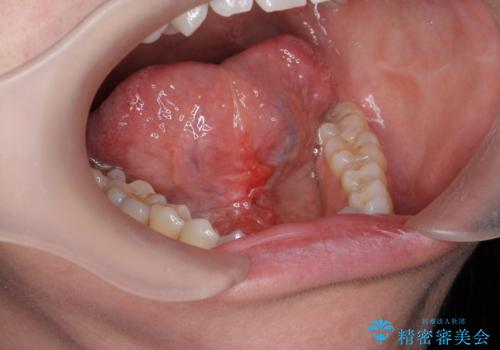

[ 舌小帯の形成 ] 滑舌の改善をしたい

担当医 大元洋佑

![[ 舌小帯の形成 ] 滑舌の改善をしたいの症例 治療前](https://seimitsushinbi.jp/wp/wp-content/uploads/2022/09/459b5062738498b637cd13998f29068e-500x350.jpg?v=1662343519)

![[ 舌小帯の形成 ] 滑舌の改善をしたいの症例 治療後](https://seimitsushinbi.jp/wp/wp-content/uploads/2022/09/2f7669bb326f4f515756a383a61feb88-500x350.jpg?v=1662343538)